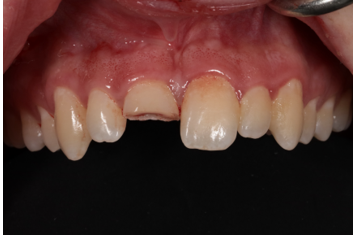

A 22-year-old patient presented to a prosthodontic practice with an complicated fracture of a maxillary central incisor (Fig. 1). The patient was transported to the dental clinic after experiencing trauma to the maxillary anterior teeth during physical fitness training. #8 displayed a mid-crown complete horizontal fracture, the pulpal tissue was exposed, no mobility, and the patient reported a moderate amount of sharp constant pain (Fig. 2). A pulpal and periapical diagnosis of symptomatic irreversible pulpitis and normal apical tissue was made. No other injuries were noted to adjacent teeth or intraoral and extraoral tissue. The fractured segment was brought with the patient and after cleaning with sterile saline it could be easily aligned back on the tooth and the margins displayed a clean fracture (Figs. 3 and 4). The patient was esthetically demanding and required a quick and long-term solution to return back to training as he was a student at Fort Eisenhower. The patient was scheduled for an overseas mission shortly after his school ended.

Figure 3: Fractured segment after cleaning with sterile saline.